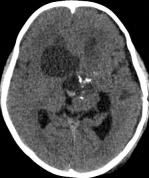

病例二:患儿女性,7岁,主因头痛2年,精神差1个月收入院。入院时头CT见典型的“超大型”颅咽管瘤,直径约9厘米,见图6。

图6.CT显示囊性颅咽管瘤

白色三角显示肿瘤边界